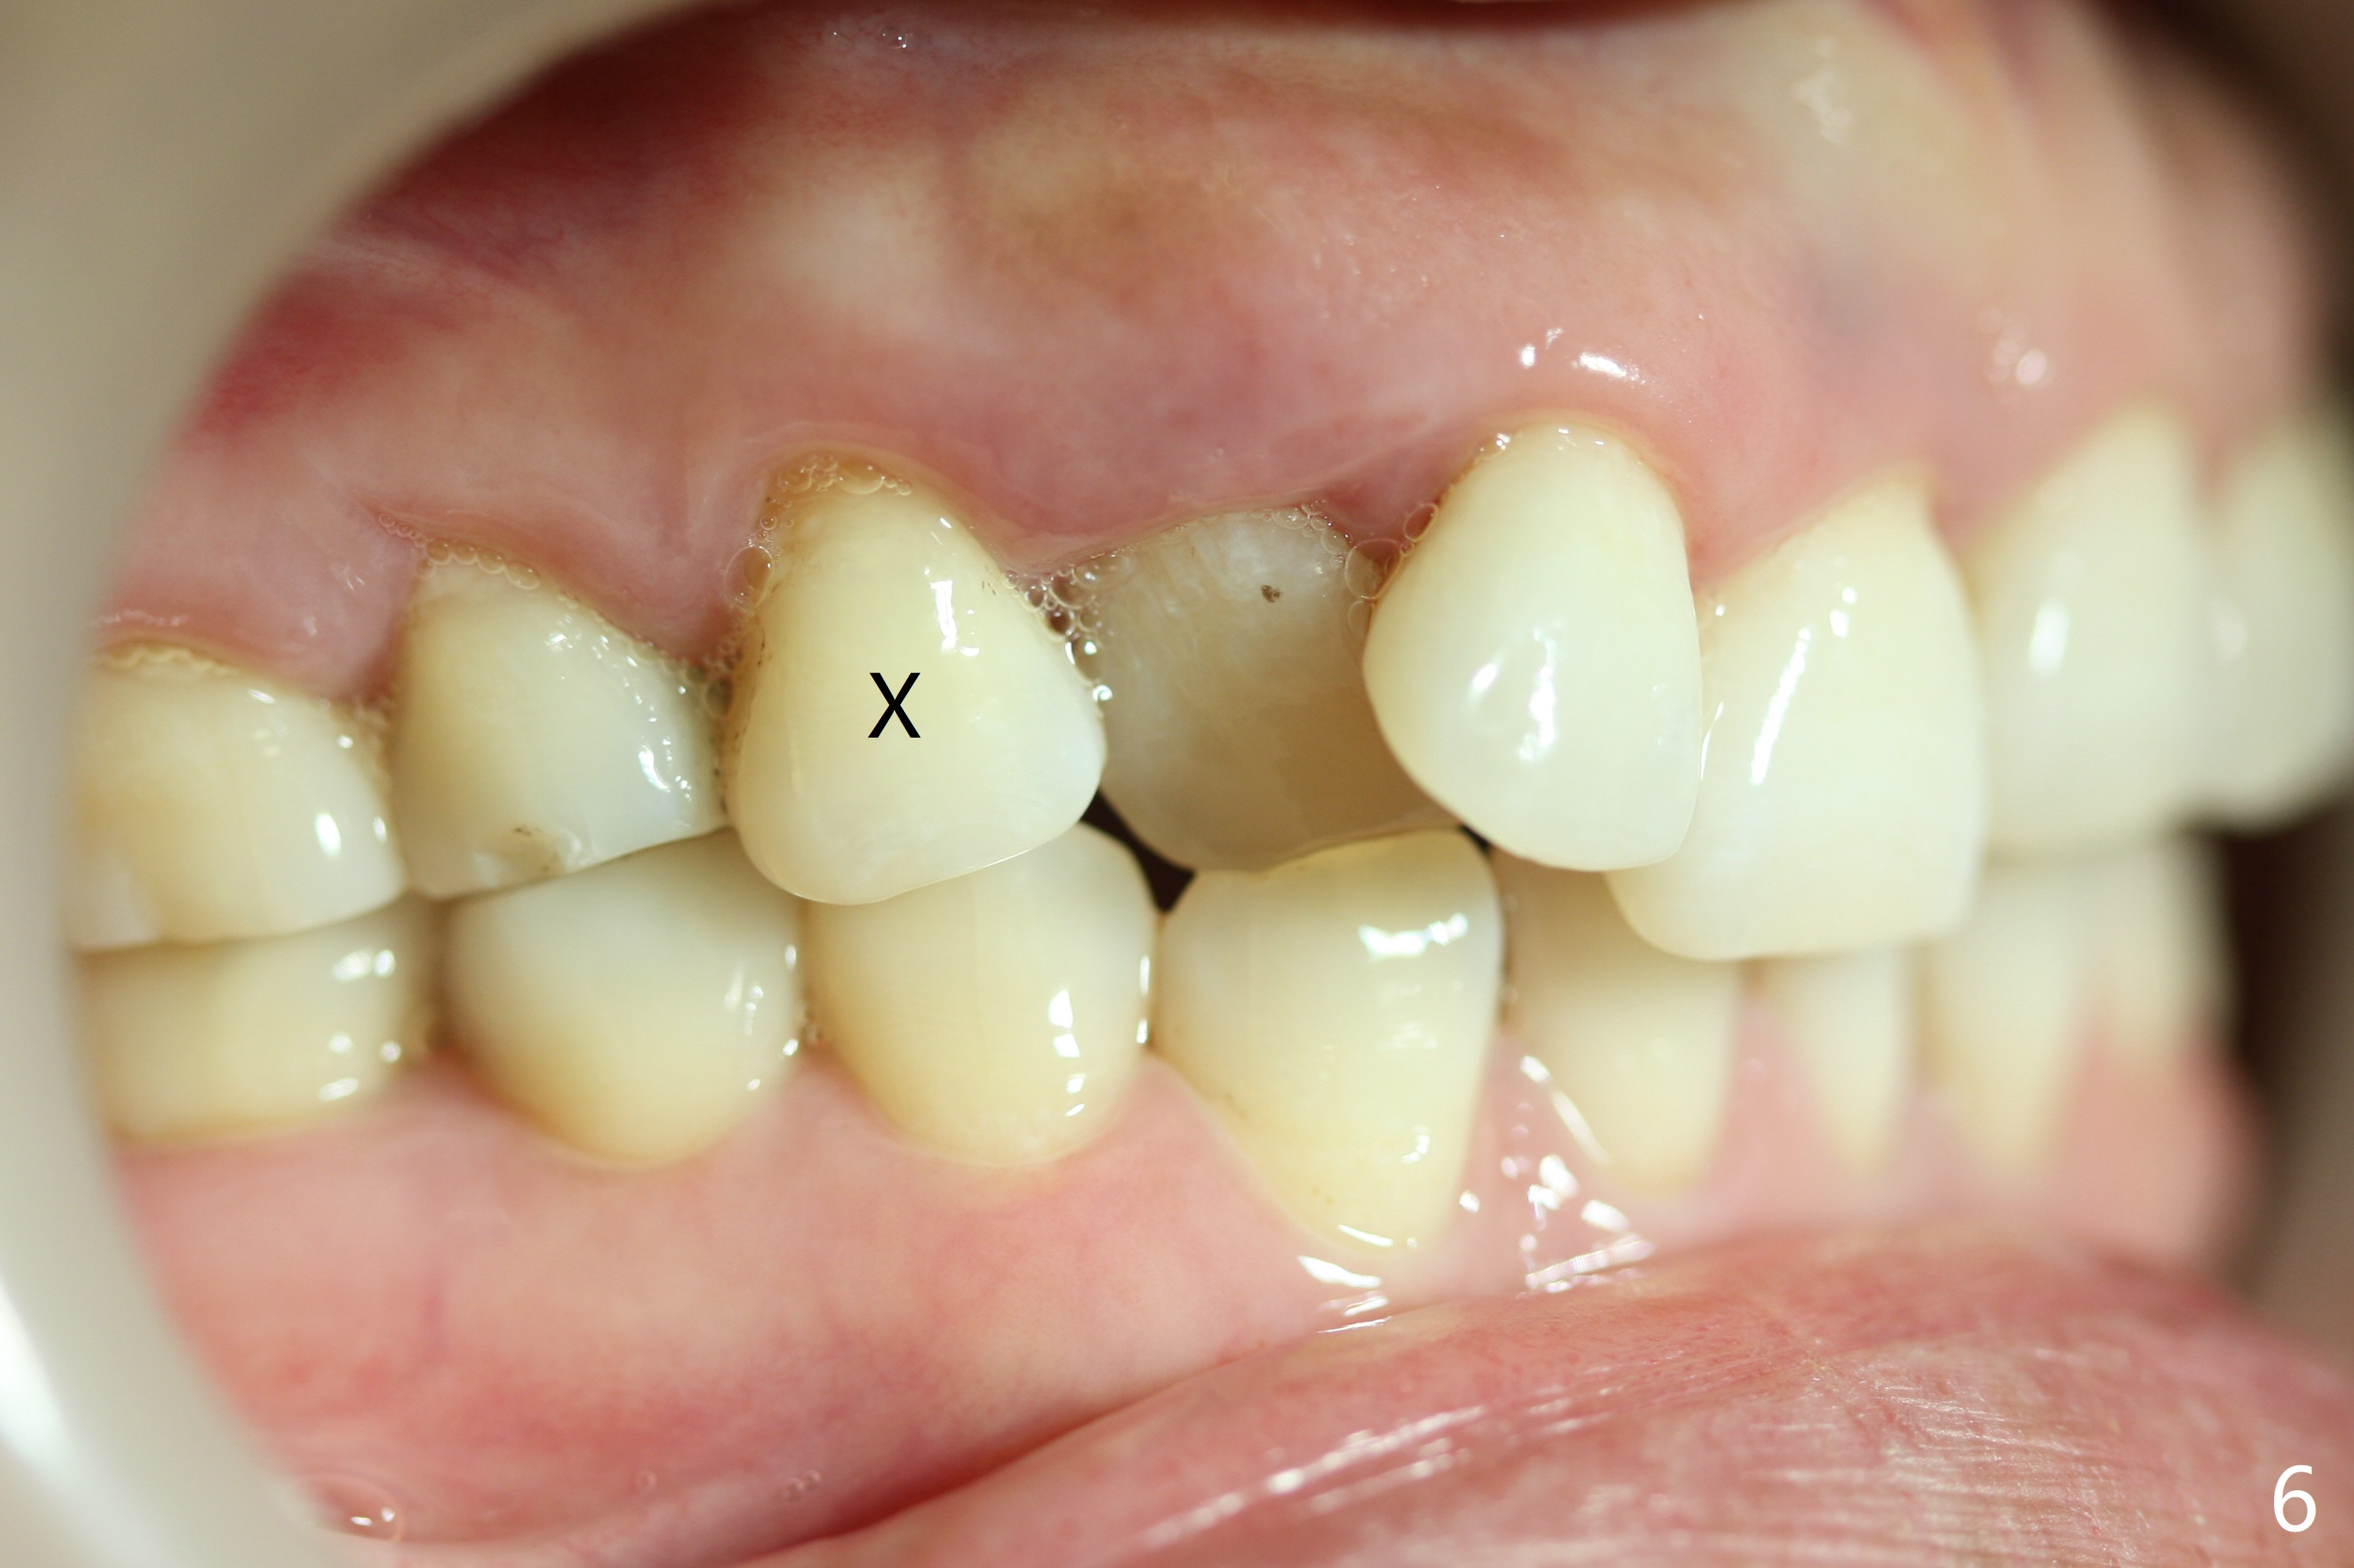

In addition, the upper dental midline deviates (Fig.2). It appears necessary to extract U4s (Fig.6,8: X) for realignment (Fig.9,11). When UR1 is intruded orthodontically (compare Fig.6,7 with 9) without increased mobility, it will be retained with lingual retainer. Otherwise it will be extracted for implant. Model surgery confirms the necessity of U4 extraction.